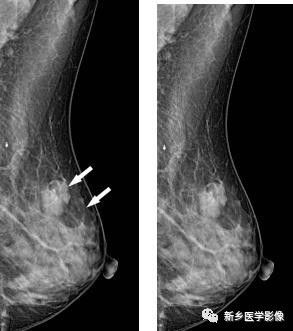

乳腺良性钙化X线图像

右乳CC位片示腺体内见散在颗粒状、小环形钙化(白箭)

乳腺恶性钙化X线图像

A和b. 右乳MLO位和CC位片示外上象限见密集细小砂粒状,呈簇状钙化(白箭)